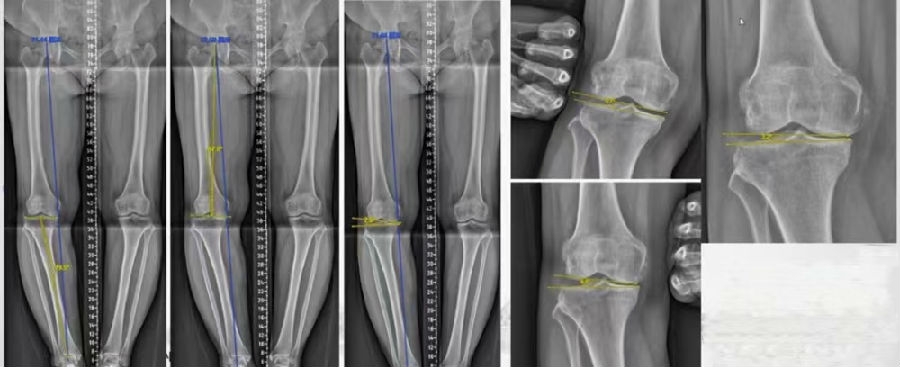

通过MAT测量全长片和内外侧应力位片,可以明确的测量出畸形的来源是股骨还是胫骨,有没有关节内磨损和韧带松弛。

MCOA病例,对线异常来源多个因素:胫骨畸形(MPTA异常),股骨形(mLDFA异常),胫骨平台塌陷,LCL松弛,内侧关节软骨丢失造成关节线不等宽等。MAT可以确定其中每种成分;应力下拍片,确定JLCA的关节松弛成分。关节软骨丢失占JLCA 3度,LCL松弛占JLCA 4度。

2、如何根据内侧间隙确定目标力线?

根据膝关节内侧间室模式程度选择个体化的目标力线。

关节间隙正常:目标MAD=0

关节间隙减少1/3:目标MAD =1/3Fujisawa

关节间隙减少2/3:目标MAD =2/3Fujisawa

关节间隙消失:目标MAD =3/3Fujisawa